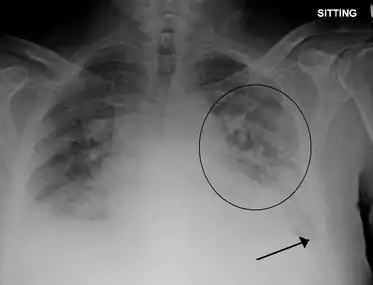

| Peripheral edema in the lower extremity that can result from volume overload following large volume blood transfusions. | |

- Evidence of acute or worsening pulmonary edema (by physical examination or chest imaging)

The clinical symptoms from TACO are due to an excess of fluid within the circulatory system. As a result, there is increased pressure within the circulatory system, resulting in fluid moving into the surrounding tissues.[4] In the lungs, the extra fluid accumulates into the air sacs within the lung, causing difficulties in oxygen getting into the blood. This results in low blood oxygen levels and shortness of breath. In the arms and legs, the fluid accumulates in the tissues, causing swelling. This is most prominent in the legs due to the effects of gravity. Conditions that predispose to increased hydrostatic pressure (heart failure and renal insufficiency) or decreased oncotic pressure (liver failure, malnutrition, nephrotic syndrome) places individuals at increased risk for TACO.